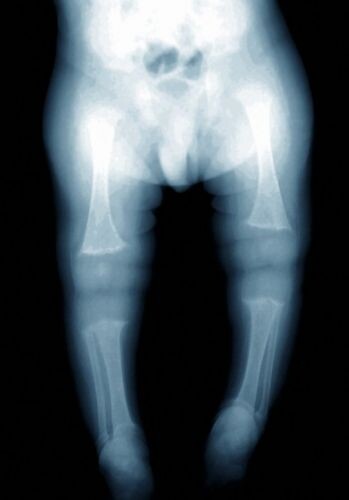

Такое «бедное» питание отразилось на здоровье. Дочку привели на обследование и были обнаружены те самые ужасные последствия от питания. В организме девочки была острая нехватка кальция, фосфата, железа, цинка, витаминов B12, A и D. Врачи переживали, что просто могут повредить кости девочки, настолько они были хрупкими. При этом снимки показали, что некоторые из костей девочки уже имели трещины.

После полного исследования, был вынесен страшный вердикт — у девочки «рахит». Это серьезное заболевание костей, которая появляется в результате дефицита минералов и витаминов. При этом в классической форме и самой первой стадии лечение возможно. В этом же случае сложно определить, можно ли девочке помочь.